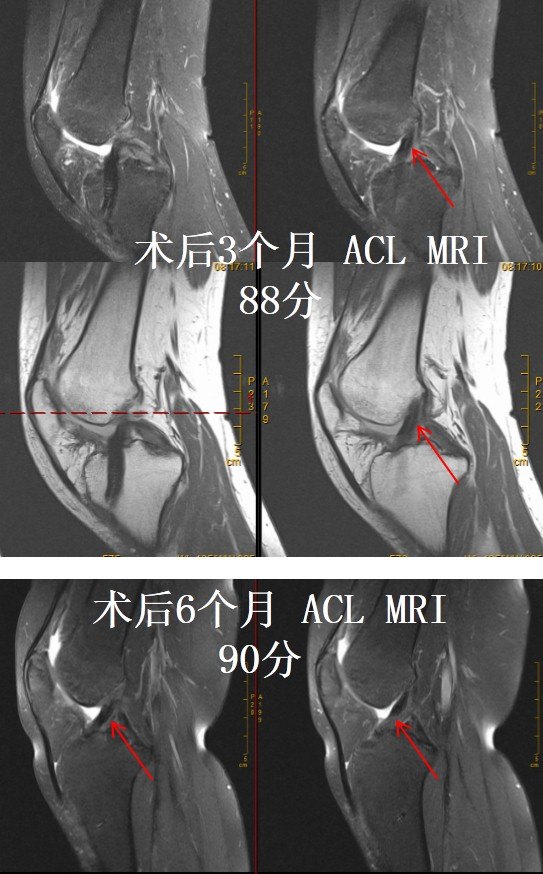

Author rihaworks70 Created Date AMACL再建術後のランニング開始時の膝伸展筋力,筋力 基準は種々報告されており,Paessler4)は術後3か月での 膝伸展筋力患健比が65%,櫻井,清水は等尺性膝伸展筋 力患健比が60~70%5)~6)としている.また,ランニンAclの再建を行った患者のうち、リハビリテーション経過を 観察できた18名(男性8名、女性10名)を対象とした mriを 用いて術後3、 4、 6、 9、 12ケ月経過時に大腿部の筋体積を 計測した。 acl再建術後の大腿四頭筋では内側広筋を中心とし